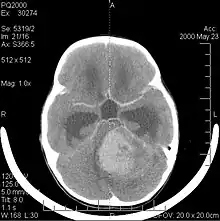

La tomodensitométrie (TDM) et L'imagerie par résonance magnétique (IRM) peuvent détecter efficacement une néoplasie dans le cerveau. L'IRM est plus sensible que la TDM pour identifier les lésions, mais présente des contre- indications pour les patients porteurs de stimulateurs cardiaques, de prothèses incompatibles, de clips métalliques et contre-indications. La TDM reste la méthode de choix pour détecter les calcifications au sein des lésions ou les érosions osseuses de la calotte ou de base du crâne. L'utilisation d' agents de contraste, iodés dans le cas du scanner et paramagnétiques (gadolinium) dans le cas de l'IRM, permet l'acquisition d'informations sur la vascularisation et l'intégrité de la barrière hémato-encéphalique, une meilleure définition de la tumeur tumorale par rapport à l' œdème environnant et à la génération d' hypothèses sur le degré de malignité. L'examen radiologique permet également d'évaluer les effets mécaniques et les modifications importantes des structures cérébrales résultant de la tumeur, telles que l' hydrocéphalie et les hernies, dont les effets peuvent être fatals. Enfin, en préparation à la chirurgie, ce diagnostic peut être utilisé pour déterminer la localisation de la lésion ou l'infiltration de la tumeur dans des zones vitales du cerveau. À cette fin, l'IRM est plus efficace que la tomodensitométrie car elle peut fournir des images en trois dimensions.

Les outils d'imagerie radiologique diagnostique mettent en évidence la modification du tissu néoplasique par rapport au parenchyme cérébral normal (par le biais de modifications de la densité tissulaire imagée électroniquement en TDM et de l'intensité du signal en IRM). Comme la plupart des tissus pathologiques, les tumeurs sont également reconnaissables par une accumulation accrue d'eau intracellulaire. Dans la tomodensitométrie, ils apparaissent hypodenses, c'est-à-dire de moindre densité que le parenchyme cérébral, dans la tomographie par résonance magnétique nucléaire avec relaxation spin-réseau hypointense et en relaxation spin-spin ainsi que l' hypersignal en pondération protonique (PD).

La tomodensitométrie du cerveau montre généralement une masse tissulaire qui peut être améliorée par l'un ou l'autre contraste. Au scanner, les gliomes de bas grade apparaissent généralement isodenses au parenchyme normal et peuvent donc ne pas présenter de rehaussement de contraste. De même, les lésions de la fosse crânienne postérieure sont difficiles à identifier au scanner. Par conséquent, les seuls résultats d'une telle tomographie ne sont pas toujours suffisants à des fins diagnostiques. Dans les cas douteux, l'utilisation de l'imagerie par résonance magnétique plus sensible est indispensable.

Sur-L'IRM montre une tumeur intracrânienne comme une lésion massive qui peut devenir plus luminescente après utilisation du produit de contraste. Cependant, il y a toujours une anomalie de signal dans -L'imagerie par résonance magnétique, qui indique la présence d'une néoplasie ou d'un œdème vasogénique. Habituellement, une luminescence accrue (amélioration du contraste) indique une tumeur d'un grade supérieur de malignité. Un anneau de contraste est caractéristique du glioblastome, avec la partie luminescente correspondant à la partie vitale de la tumeur maligne, et la plus foncée - zone hypointense correspondant à une nécrose tissulaire.